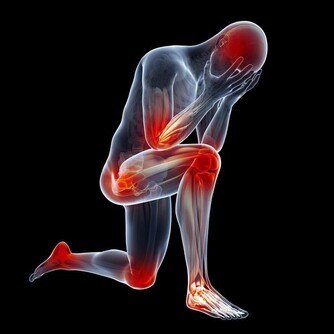

Q1:高尿酸是怎麼來的?

人體尿酸有兩種來源:一是內源性的,是有身體內的氨基酸、核酸等分解而代謝出來,約佔80%;二是外源性的,是有吃的食物中的核苷酸分解代謝而出,佔20%左右。

所以,飲食在高尿酸症的發生中雖然有重要的影響,但是也不是唯一的影響因素。

如果是原發性的高尿酸血症,採用低嘌呤的飲食,雖然可以降低尿酸水平,但是因為身體內已經含有大量的尿酸鹽沉積在關節腔內,必須用藥無治療才能降低尿酸的水平,

但也不是說,就不需要在飲食上加以控制了。如果暴飲暴食,在段時間尿酸也會有顯著的上升,從而誘發急性痛風。